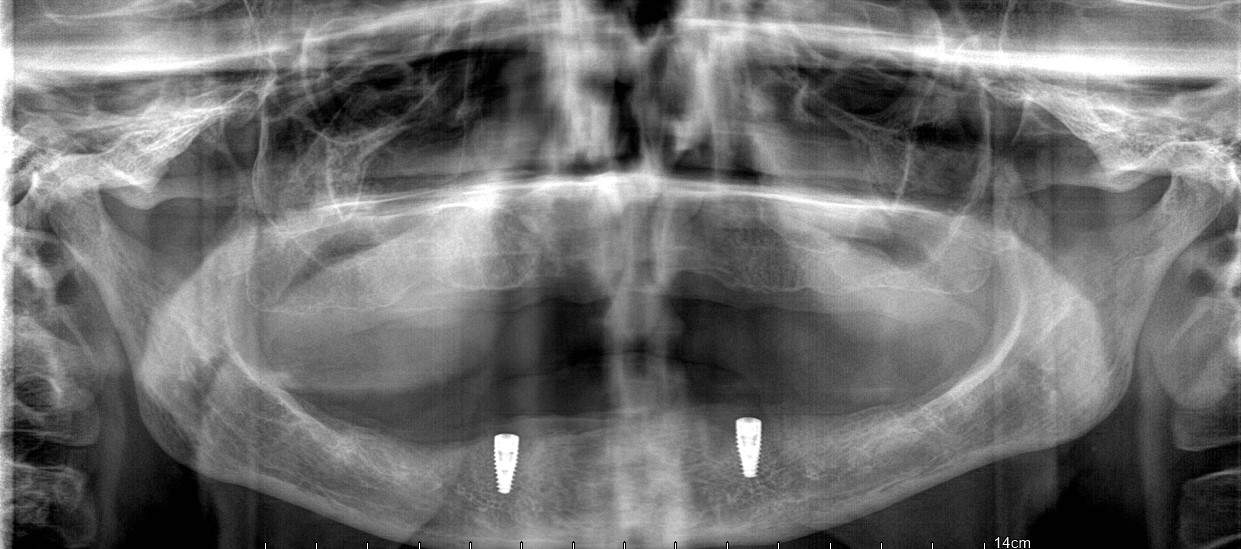

Proteza overdenture na dwóch implantach

Protezy overdenture, zwane inaczej nakładowymi protezami szkieletowymi bezklamrowymi, to uzupełnienia ruchome, które stosuje się do uzupełniania braków zębowych wspartych na implantach. Protezy overdenture wykazują szereg zalet w porównaniu z całkowitymi protezami ruchomymi. Oto kilka przykładów: